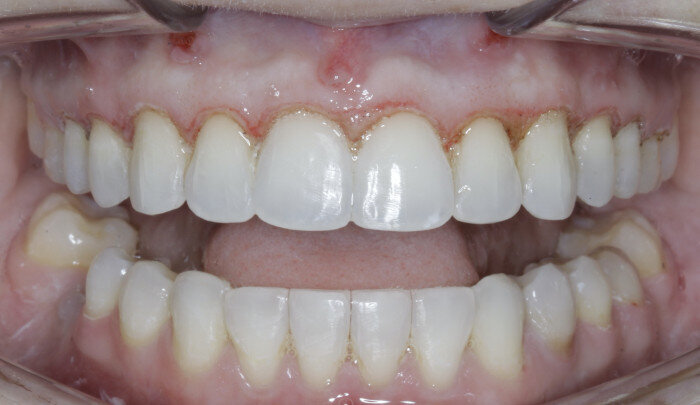

Once the intrusion has been completed, the TADs are tied to the wire and vertical elastics are used to close the bite without relapse of the intrusion. If buccal crown tip is seen, owing to the movement created by the intrusion, a power chain torquing sling is used to encourage lingual crown tipping and to prevent flaring of the incisors (Fig. 9). Once the case has been completed, the appliance is removed and a gingivectomy is performed to idealise the tissue shape and the final contours are made to the hard tissue (Figs. 10–12, end of treatment).

Fig. 6

Fig. 7

Fig. 8

Fig. 9

Fig. 10

Fig. 11

Fig. 12